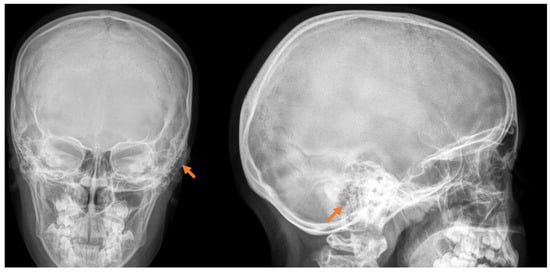

This case study involves a 13-year-old female patient who, at the age of 7, noticed a slight painless swelling in the left retroauricular region. The first diagnosis of the tumor was made with radiography.

Over a six-year period, it had significantly increased in size with visible cosmetic deformity. The patient had mild pain, especially when lying on the same side, without any other functional disturbances (Figure 2).

The clinical course of osteomas is often asymptomatic, and they are usually diagnosed incidentally. Depending on the localization, they may present with facial deformities, ocular manifestations (exophthalmos), and headaches [7]. The diagnosis of osteomas can be made by skull radiography/skull X-rays (occipitomental projection, also known as Water’s view) or computed tomography without contrast enhancement, which has many more advantages. Computed tomography with 3D reconstructions allows for the detailed visualization of osteomas and their specific localization in relation to other vital structures (the orbit, anterior, medial, and lateral skull base, facial nerve and intracranial structures). It can also determine the attachment of the osteoma to the cortex in the case of mastoid processes—pedunculated or sessile [8]. The study is also useful in the differential diagnosis of osteoma and other mastoid bone tumors, especially osteosarcoma, bone metastases, multiple myeloma, giant cell tumor, Paget’s disease-associated lesions, or fibrous dysplasia [1,6,7,9]. Signs suggesting a malignant lesion are rapid growth, local pain, and a poorly differentiated, heterogeneous, osteolytic appearance on CT [9]. Mastoid osteomas are slow-growing and can seldom be indicated for surgical treatment in the early stages. The cosmetic defect that they would create is the most common reason for surgical removal. Osteoma removal is performed through a retroauricular incision exposing the tumor and its radical removal using a curette or burr. The presentation of intact mastoid cells is normal and does not pose a risk. Sometimes, a slightly prominent sinkhole can possibly occur postoperatively in this area. Histological examination is important to confirm the diagnosis and specify the histological type—compact, spongy, or mixed. Compact or combined is most often found, and spongy is much less common [10].

Figure 1. Radiological examination in front and side view, with the detection of a slight deformation along with bone growth in the cortical area of the mastoid process, pointed with orange arrow.